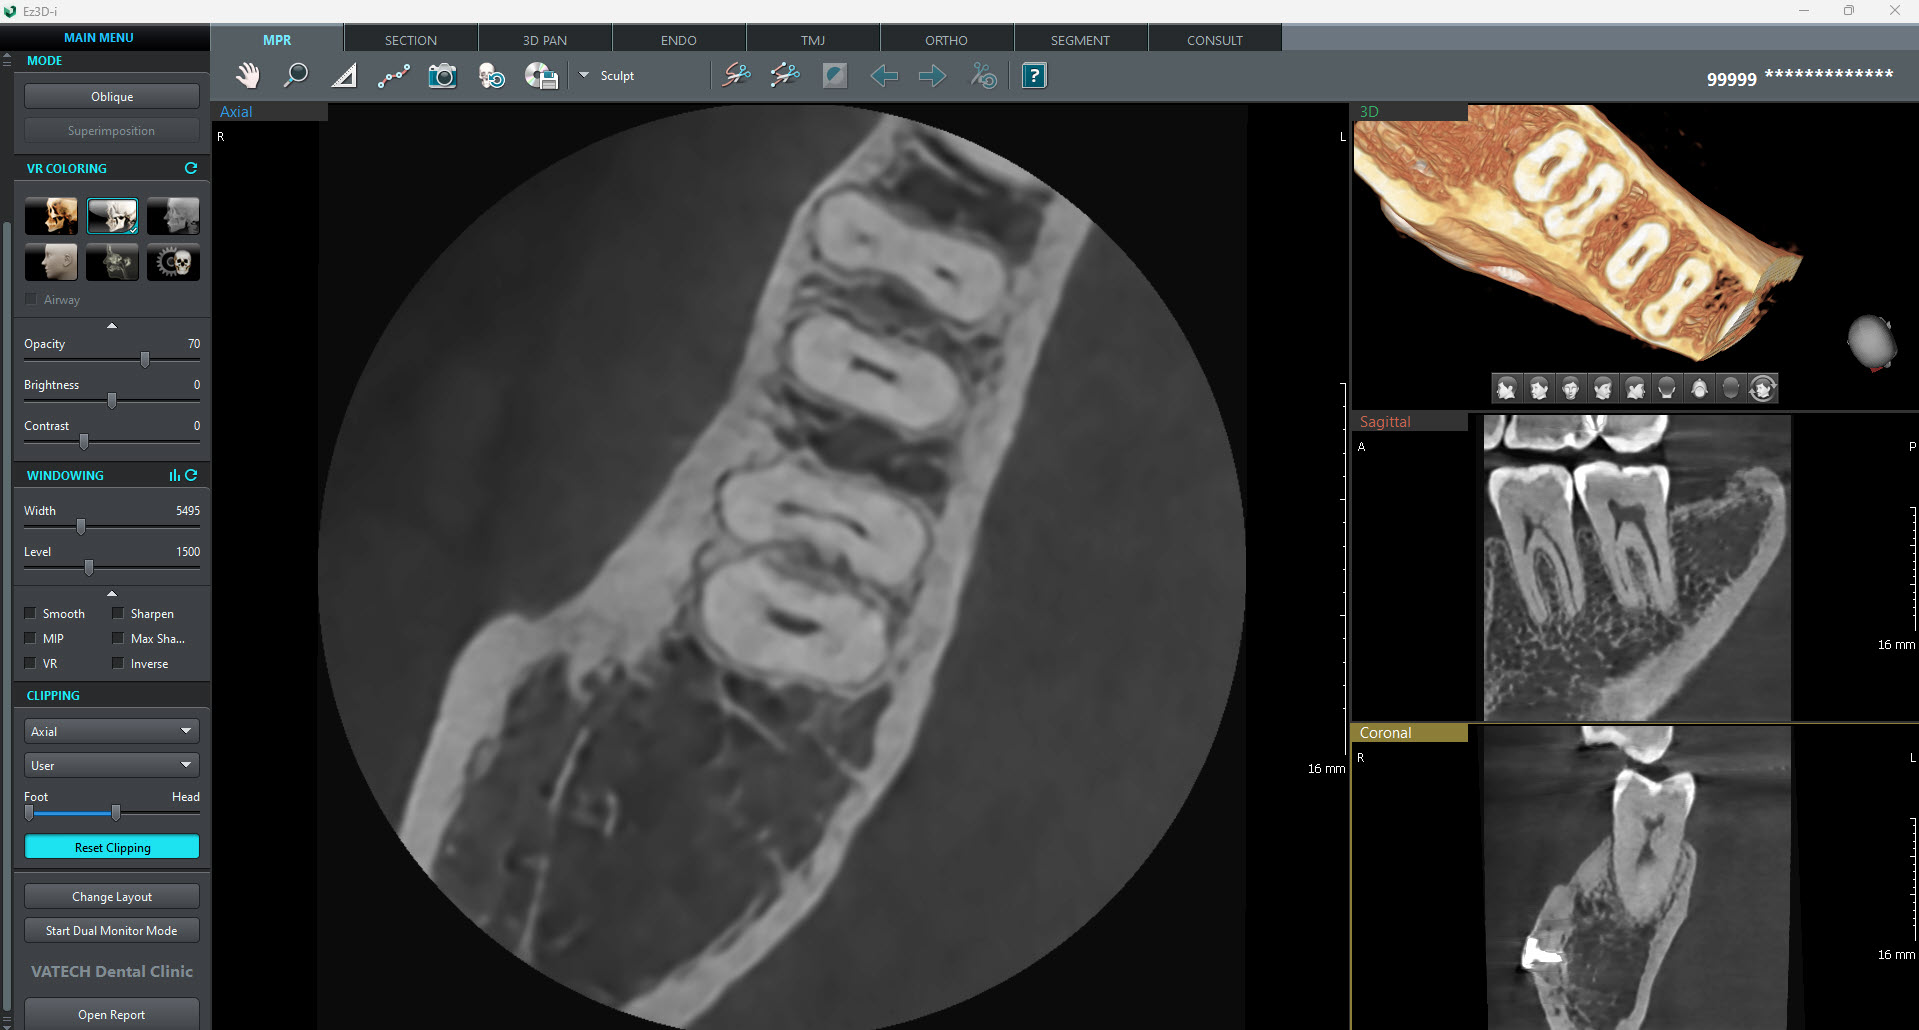

2D AND 3D IN ONE VIEWER

Viewing 2D and 3D images together provides many benefits. There is no need to utilize two different

software programs and the One Viewer feature presents a professional look for your patients.

This layout helps patients better understand the images, which will eventually result in increasing

acceptance rates.